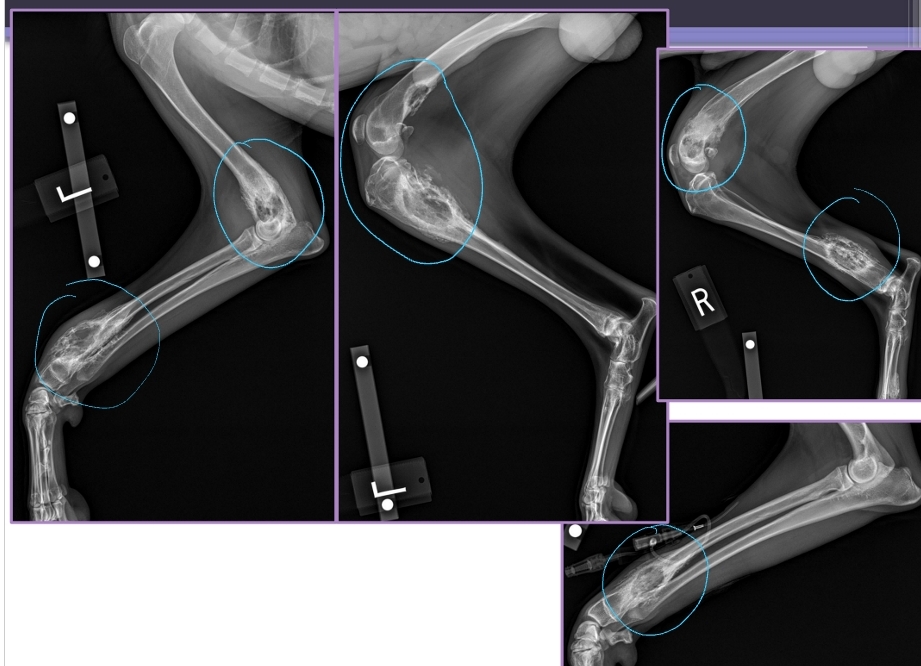

Primary Bone Neoplasia

Et: Osteosarcoma, Chondrosarcoma

Cs: Lameness, Muscle atrophy, Bone swelling

Dt: Radiographs #1, CT, Bone biopsy

Osteolysis, Osteoproliferation, Soft tissue swelling

“Away from the elbow, toward the knee”

proximal humerus, distal radius/ulna & distal femur, proximal tibia

Tx:

Amputation: Eliminates pain, MST 6 months

Amputation + Chemo: Eliminates pain, MST 12 months

Primary Stabilization + Chemo: Allows mobility, MST 12 months

Chemo adds extra time of survival!!